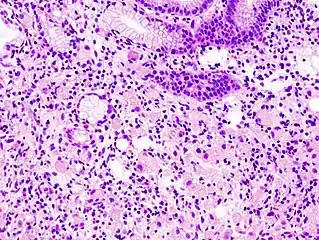

In histology, a signet ring cell is a cell with a large vacuole. The malignant type is seen predominantly in carcinomas. Signet ring cells are most frequently associated with stomach cancer,[1] but can arise from any number of tissues including the prostate,[2] bladder, gallbladder,[3] breast, colon,[4] ovarian stroma and testis.[5]

The name of the cell comes from its appearance; signet ring cells resemble signet rings. They contain a large amount of mucin, which pushes the nucleus to the cell periphery. The pool of mucin in a signet ring cell mimics the appearance of a finger hole and the nucleus mimics the appearance of the face of the ring in profile.

A significant number of signet ring cells, generally, are associated with a worse prognosis.[6][7]